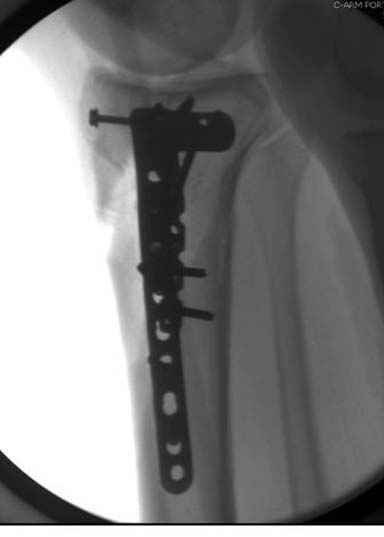

Решили выполнить остеосинтез штифтом и внутрисуставного перелома пластиной и винтами. Жду мнения! Зачем мне оправдываться-я же не преступник. Диалогом называется...

При переломах одного из мыщелков тибиал плато+дополнительный перелом проксимальной трети большеберцовой кости можно применить комбинированный вариант фиксации, т.е. мыщелок винтами или пластиной, а для диафиза можно установить гвоздь. В данном варианте потеряно преимущество гвоздя , из-за серьезной травмы суставной поверхности нельзя нагружать ногу несколько месяцев. А без нагрузки гвоздь просто заполнитель пространства внутри кости!

Здесь пару случаев для сравнения,...в первых 1-4 слайдах метод фиксации одним фиксатором, как видно после 8 месяцев сохранилась ось. С 5 по 9 вариант двумя пластинами...